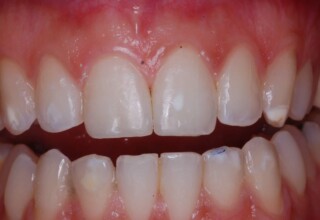

Restoration of bilateral diastemas between central and lateral incisors.

Diastemas were created mainly because of narrow laterals. After orthodontic treatment was finalized, the diastemas were closed with two composite resin restorations.